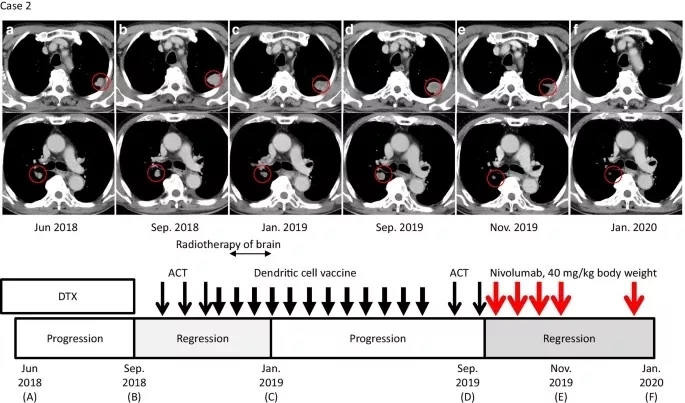

日本男性患者,于2016年6月被诊断为食管癌,时年77岁。CT和活检标本显示食管鳞癌临床Ⅳ期(UICC, T4N2M1)。于2017年7~11月接受氟尿嘧啶/铂的CCRT。2017年12月,胃镜检查显示食管癌完全缓解。患者于2017年7月至11月接受氟嘧啶/铂CCRT。2017年12月,胃镜检查显示食管癌完全缓解。患者一直为无疾病状态,直到2018年4月,常规CT显示双侧肺和右肺门淋巴结多发转移(图2a)。2018年5~9月,患者接受多西他赛作为二线化疗,但发现其肺转移已进展(图2b)。

患者于2018年10月至作者医院接受ACT,随后以2~3周的间隔进行3次αβT淋巴细胞的ACT,直到2018年12月。2018年12月26日到2019年6月28日,患者共接受了12次(间隔2~3周)应用MUC1、MAGE3和survivin的树突状细胞(DCs)脉冲治疗(图2),MUC1、MAGE3和survivin均作为肿瘤抗原在其肿瘤细胞上表达。在ACT和脉冲DC治疗期间,2018年11月发生脑转移,接受了脑转移立体定向放疗。常规CT显示,多个肺和淋巴结的转移病灶缩小,根据2019年1月实体瘤反应评价标准(RECIST)1.1版评估为部分缓解(图2c)。此外,2019年4月脑转移病灶也有所减少。

2019年9月,随访CT显示肺和肺门淋巴结转移灶再生,患者开始每月接受一次ACT治疗(图2d)。免疫组化染色显示肿瘤中PD-L1表达水平为1%,MSI阴性(数据未显示)。ACT后,患者接受纳武利尤单抗治疗(剂量为0.6 mg/kg体重,4次,每隔2周一次)作为诱导治疗的一部分。

2019年11月27日(纳武利尤单抗启动后8周)的随访CT扫描显示部分缓解,肺部病灶及和肺门部淋巴结肿块减少60%(图2e)。患者继续接受每隔3周一次、剂量为40 mg/kg体重的纳武利尤单抗治疗作为维持治疗。在患者2019年的临床病程中,放射学证据显示病变持续改善,由于患者临床状态良好且存活,因此继续使用纳武利尤单抗维持治疗(图2f)。在联合治疗期间没有不良事件的证据。

图2. 病例2临床病程

与治疗和疾病状态时间线相对应的轴位CT图像。红色圆圈表示肺和肺门转移性病变。a. (上)多西他赛(DTX)给药期间的状态。b. 过继细胞疗法(ACT)治疗前肺转移进展情况。c. ACT和树突状细胞(DC)疫苗治疗后肺转移的消退。d. 服用纳武利尤单抗前肺和肺门淋巴结转移的进展。e. 免疫检查点抑制剂(ICI)与ACT联合治疗8周后肺转移消退。在使用ICI维持治疗期间,缓解是持续的(f)。窄的黑色箭头、粗体黑色箭头和红色箭头分别表示ACT、DC疫苗和纳武利尤单抗给药(下)。